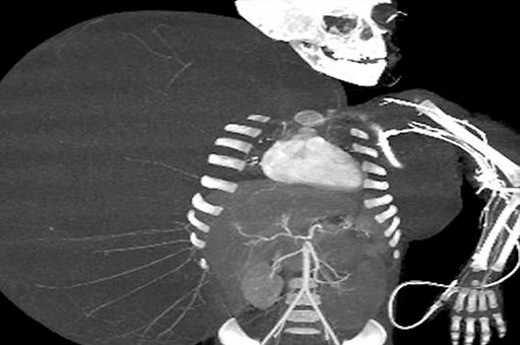

Abone olMeksikalı doktor Gustavo Hernandez, 14 Haziran’da yapılan ameliyatla 2 yaşındaki erkek çocuğunun vücudundan kendi ağırlığından daha fazla olan 15 kilogramlık bir tümör çıkarıldığını, çocuğun 12 kilogram ağırlığında olduğunu söyledi.

Hernandez, ülkenin kuzeyinde Durango eyaletinde yaşayan ve zamanla koltuk altından kalçasına kadar vücudunun sağ tarafını kaplayan tümörle doğan çocuğun La Raza Tıp Merkezi’nde yapılan ameliyatının 10 saat sürdüğünü kaydetti.